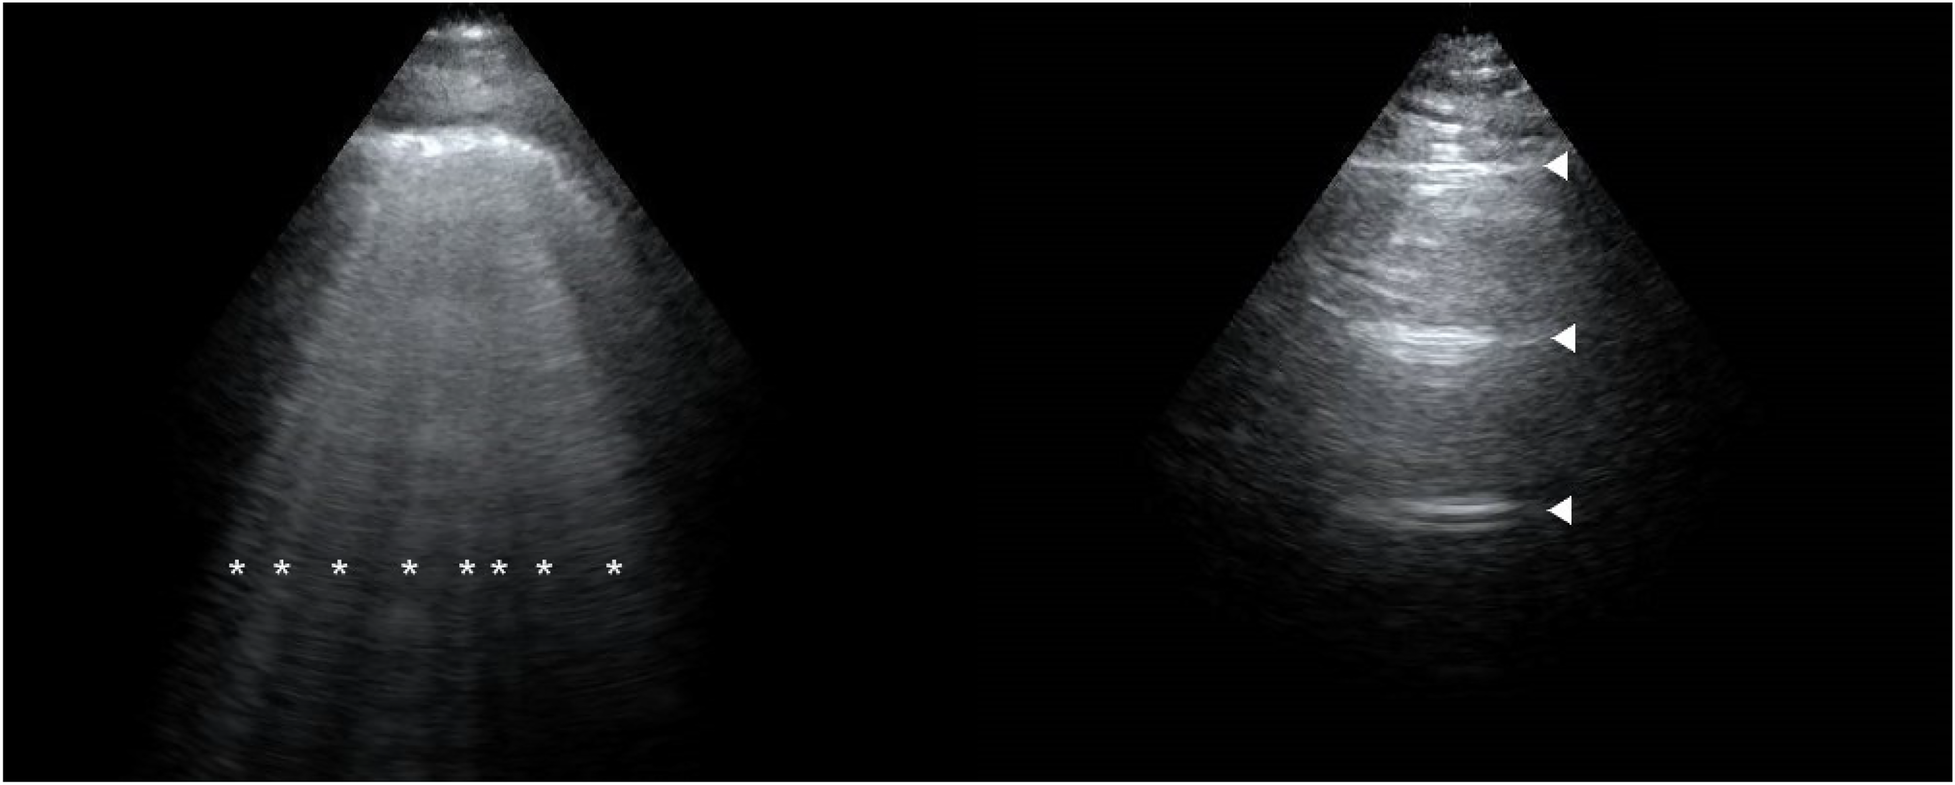

The ECS in the PE group was greater than that in the control group at 24 h before delivery, 2 h postpartum, and 24 h postpartum (all P < 0.001). With respect to the degree of EVLW increase, at 24 h before delivery, nine patients in the PE group presented mild increases, whereas none in the control group did. At 2 h postpartum, 11 patients in the PE group presented mild increases, and 1 patient presented moderate increases, whereas 5 patients in the control group presented mild increases. At 24 h postpartum, six patients in the PE group presented mild increases, two patients presented moderate increases, and one patient in the control group presented mild increases (Table 2). Figure 1 shows the lung ultrasound performance of PE patients and healthy controls at 2 h postpartum.

Figure 1

Lung ultrasound performance of a preeclampsia patient (left) and a healthy patient (right) at 2 h postpartum. The image of a preeclampsia patient is filled with B-lines (*). The image of a healthy patient is shown as A-lines (▴).